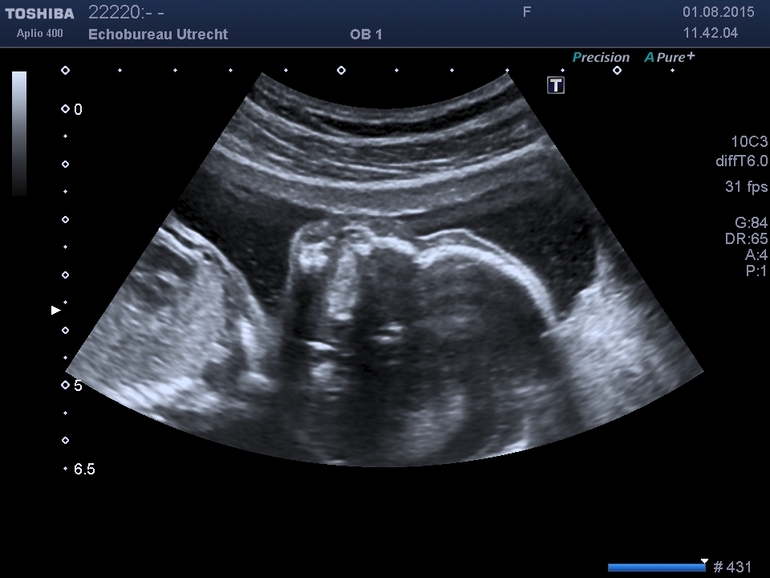

Итак, уже почти неделя как я активно чувствую шевеления своего малыша. При чем чувствую очень часто - почти каждый раз, как сажусь и ложусь куда бы-то не было. Что и подтвердилось сегодня на УЗИ: узистка сказала что впервые видит такого активного ребенка на этом сроке =)

Хотя узистке стоило большого труда поймать нужные позы детеныша, все-таки после 40 минут мучений все нужные замеры были произведены и аномалий или особенностей не выявлено. Сложность захвата органов немного облегчало то, что по словам узистки я идеальный человек для проведения УЗИ - не поняла что именно она имела в виду, но сказала что ей очень легко смотреть внутрь меня...

Ну и также подходя к серебине конечно начинают потихоньку появляться страхи - а как же я буду это маленькое существо из себя выталкивать? =) Но опять же сегодняшнее УЗИ показало что голова у нашего малыша немного меньше среднего показателя, в то время как окружность животика больше. так что я себя успокаиваю что даже если ребенок в целом будет крупным (папа- голландец, у них средний рост что-то врое 180 =), может голова будет не очень крупной =) Ну и вот картинка. К сожалению, не дали картинку пениса крупным планом - надо было попросить =(